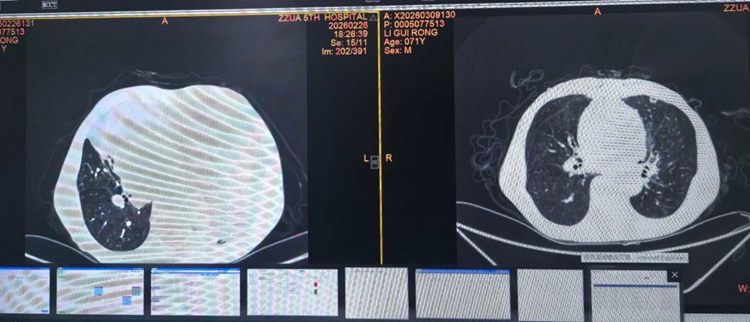

▲ 术前(左侧)与术后(右侧)肺窗对比

▲ 术前(左侧)与术后(右侧)纵隔窗对比

▲ 术后复查纵隔窗(左侧)与肺窗(右侧)

在胸外科医护团队的精心治疗与护理下,老人术后恢复顺利,胸闷症状完全消失,各项生命体征平稳,对恢复情况非常满意。术后病理结果证实为纵隔脂肪肉瘤,但由于手术切除完整,为老人的长期预后和高质量生活奠定了坚实基础。